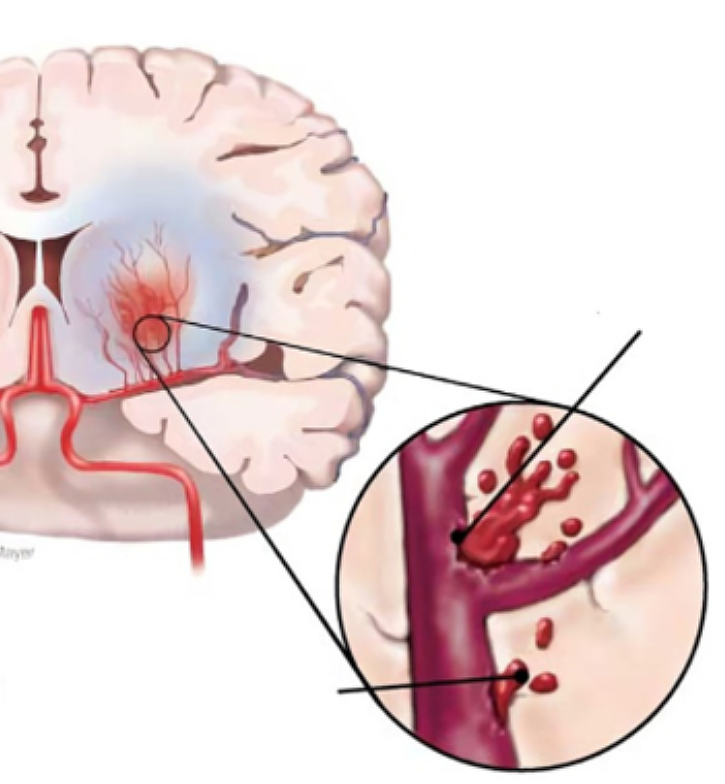

뇌졸중은 뇌 일부분에 혈액을 공급하는 혈관이 막히거나 터지면서 뇌가 손상돼 신경학적 이상이 나타나는 병입니다. 밤과 낮 그리고 실내외 온도 차가 계절에는 혈압 상승과 혈관 과부하로 심뇌혈관 질환 발병 우려가 매우 높습니다.

뇌에 혈액을 공급하는 혈관이 막히게 되면 뇌의 일부가 손상되는 ‘뇌경색 증상’, 뇌혈관이 터져 주변 뇌가 손상되는 ‘뇌출혈 증상’이 있습니다. 두 질병 모두 사망에 이르거나 뇌손상으로 인한 후유증이나 신체장애를 남길 수 있는 위험한 질환입니다.